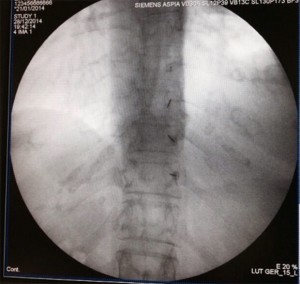

Se coloca al paciente en decúbito prono con una almohada debajo del tórax para magnificar la cifosis torácica y ampliar el sitio de entrada. Las manos se cruzan por encima de la cabeza del paciente, el cual tendrá la cabeza girada mirando hacia el lado contrario de la posición del médico. El paciente debe estar despierto, bien sea con sedación superficial o simplemente anestesia local si es colaborador. Se localiza el nivel afectado con una proyección en AP, identificando el punto de entrada en el espacio intervertebral. Luego se moviliza el rayo en el plano axial (cráneo-caudal) para ampliar el espacio intervertebral y borrar el doble contorno de los cuerpos vertebrales, y una vez hecho esto se marca el punto de entrada, que usualmente será 1-2 niveles por debajo del espacio intervertebral que se quiere alcanzar y 1 cm lateral a la apófisis espinosa (abordaje paramedial).

Se infiltra la piel con anestésico local (5-10 ml de lidocaína 1%) y después se hace la técnica epidural con una aguja tuohy 18-20G. Después de atravesar la piel se avanza la aguja inclinándola levemente hacia superior y medial para hacer contacto con la lámina. Una vez alcanzada la lámina se retira el fiador y se conecta la jeringa de baja resistencia; luego se redirige la aguja dándole una angulación de 45° en el plano sagital y 15° hacia medial; antes de avanzar se debe comprobar con el rayo en lateral que la aguja se encuentra entre las dos apófisis espinosas. Se recomienda también seguir avanzando lentamente y con guía fluoroscópica para evitar el daño medular directo con la aguja.

Una vez se nota la pérdida de resistencia se inyecta contraste y se debe dibujar una línea en la base de ambos procesos espinosos, con el rayo aún en posición lateral.